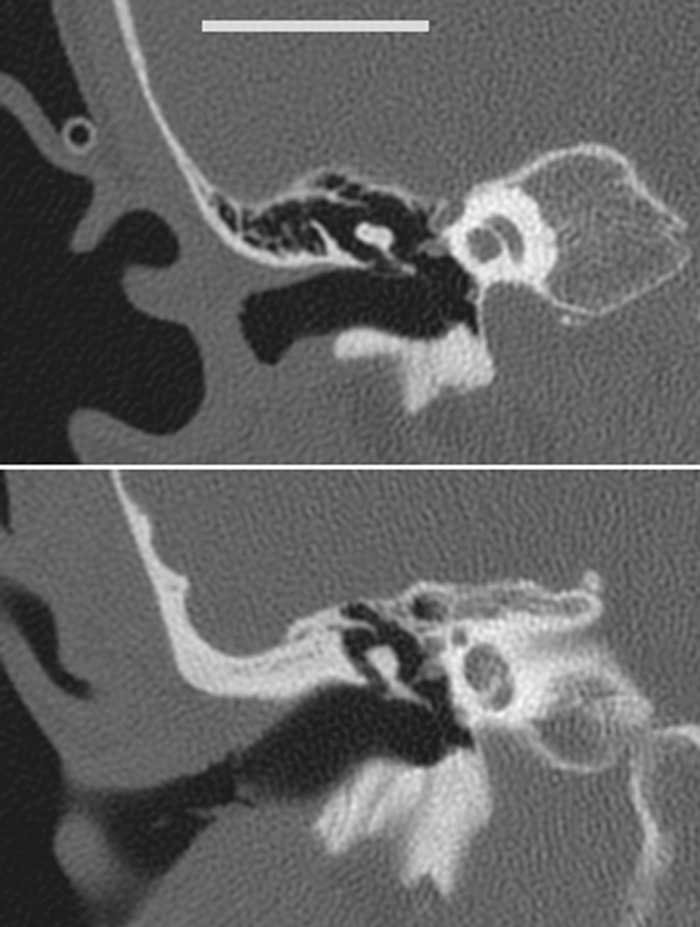

It is important to note that although the ear canal is noticeably narrower in young children than in adults, it is also significantly shorter and generally straighter. Greater freedom to manipulate the angle of endoscope and surgical instruments is possible than in a longer ear canal which helps offset the narrower diameter (Figure 5). As a result, TEES is feasible even in children under three years of age. When access is restricted by bone, the curette, drills or other powered bone removal tools (e.g. piezo-electric or ultra-sonic) can be used alongside the endoscope, making it possible to complete even more cases with TEES.

Figure 5. Coronal CT scans of the temporal bone from a 2.7-year-old child (upper panel) and a 17-year-old (lower panel; white bar = 2cm scale). Totally endoscopic surgery is feasible in young children as the ear canal is shorter and straighter in younger children, despite being narrower.